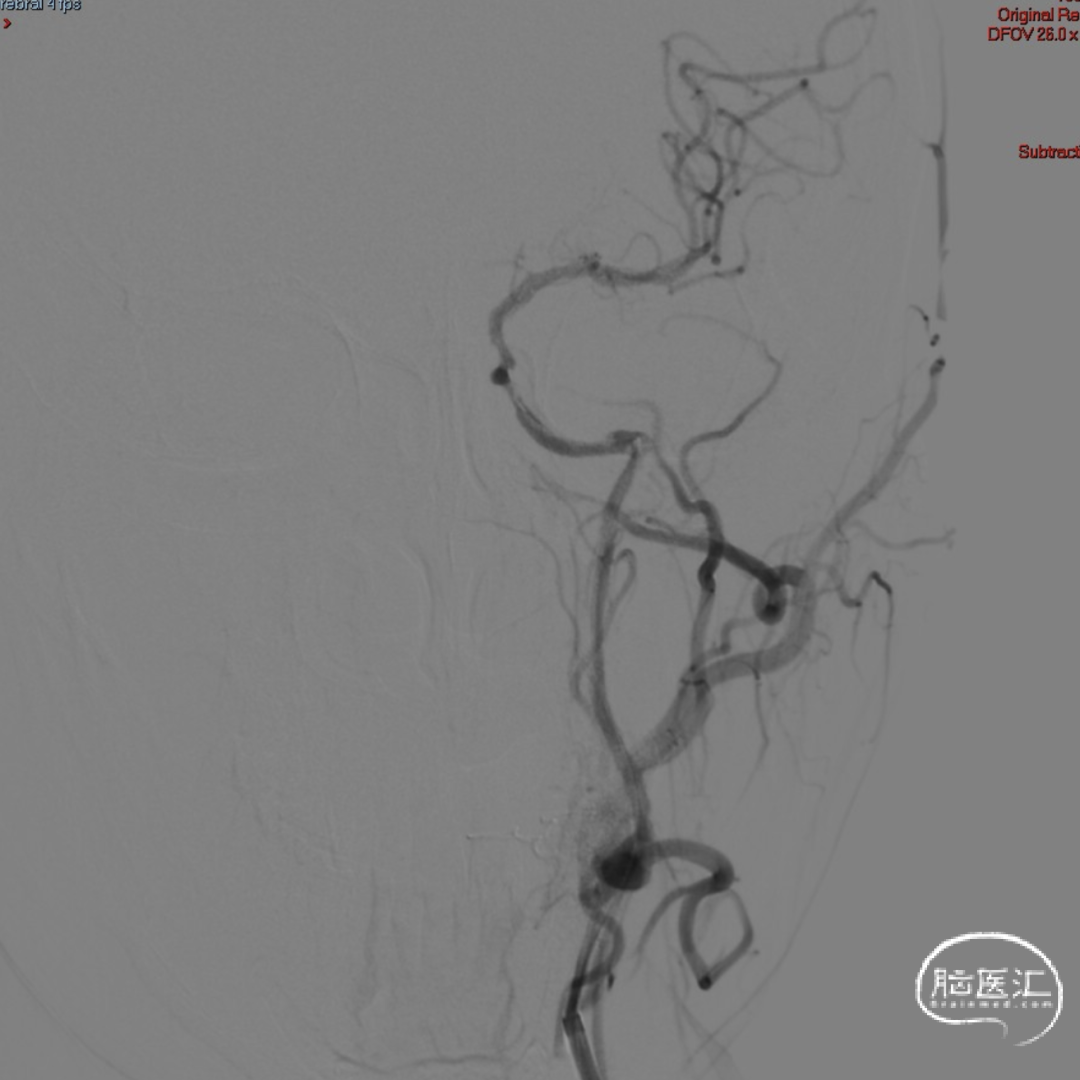

术前DSA造影显示左侧颈内动脉自起始段闭塞,C6眼段以上供血区由颈外动脉眼动脉反向代偿供血,左侧大脑中动脉供血区由前交通动脉代偿供血。

造影后引导下,以0.014in×185cm 微导丝小心通过右侧颈内动脉C1段闭塞处至C3段。随后以0.014in×300cm 微导丝在SL-10微导管支撑下通过闭塞段,成功进入大脑中动脉M1段。

沿微导管送入4.0×30mm Syphonet®取栓支架,于M1-C7段释放作为栓塞保护装置。

沿4.0×30mm Syphonet®取栓支架输送导丝送入3.0×12mm SacSpeed®球囊扩张导管,自C1-C7段分次扩张,每次释压后跟进中间导管至C5段,复查造影显示血流通畅。